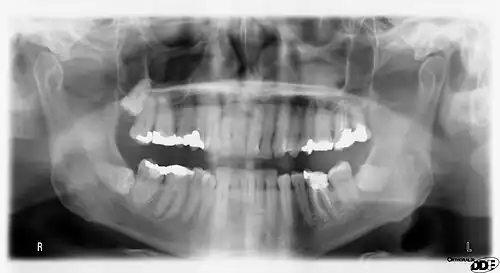

A panoramic radiograph of a 9 year old in mixed dentition

A basic panoramic radiograph